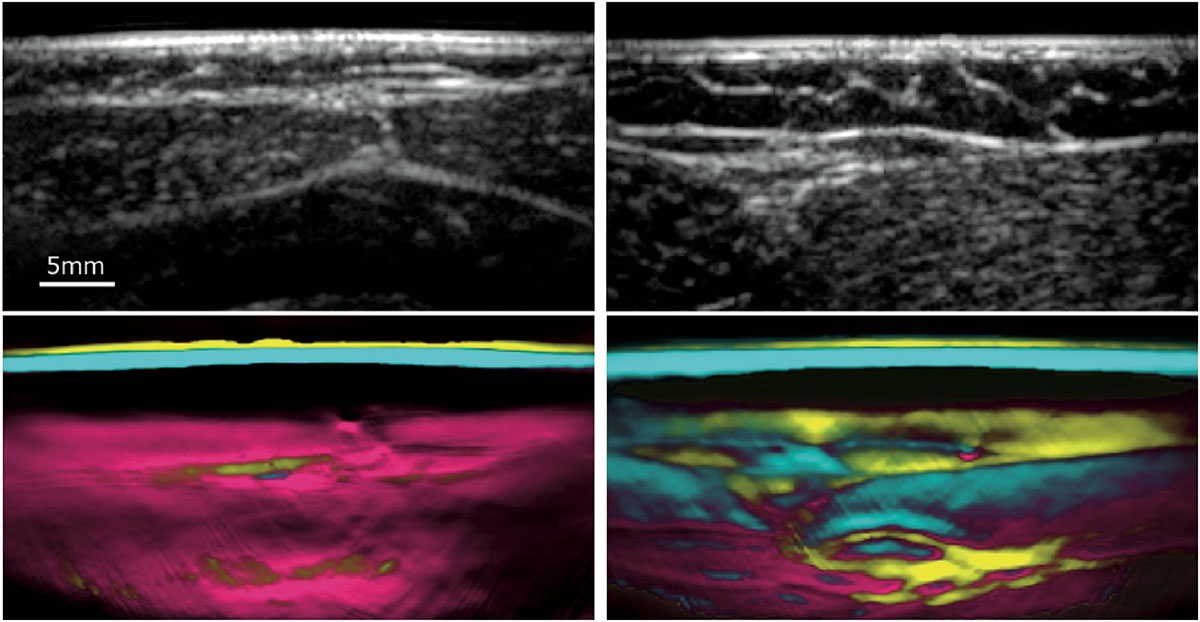

Diese Methode hat ein Team der Kinder- und Jugendklinik und der Medizinischen Klinik 1 – Gastroenterologie, Pneumologie und Endokrinologie – des Universitätsklinikums Erlangen sowie des Genzentrums der Ludwig-Maximilians-Universität München nun offenbar gefunden: In aufwändigen Tests – zunächst an Schweinen, später an betroffenen Patientinnen und Patienten – hat die Arbeitsgruppe untersucht, inwieweit sich die multispektrale optoakustische Tomographie (MSOT) für die Diagnose der Muskeldystrophie eignet. Das Verfahren wurde vor wenigen Jahren an der Technischen Universität München zusammen mit der Firma iThera Medical GmbH entwickelt: Bei der MSOT werden Pulse eines Nahinfrarot-Lasers in das Gewebe gesandt. Dabei entstehen akustische Druckwellen, anhand derer sogenannte Chromophore – körpereigene Farbstoffe – visualisiert werden können. „Wir nutzen die MSOT, um das Kollagen in den Muskeln zu quantifizieren“, erklärt Dr. Adrian Regensburger, Erstautor der Publikation und Forscherkollege von Ferdinand Knieling an der Kinderklinik. Kollagen ist ein zentraler Bestandteil des Bindegewebes – jenes Gewebes also, das die Muskeln im Krankheitsverlauf ersetzt. „Unsere Tests haben gezeigt, dass der gemessene Kollagengehalt sehr stark mit dem Funktionsstatus der Patienten korreliert.“

Mit dem neuen Verfahren können die Medizinerinnen und Mediziner also einen Biomarker nutzen, der bei der herkömmlichen Behandlung der Duchenne-Muskeldystrophie gefehlt hat. Die MSOT ist strahlungsfrei, nicht-invasiv und kommt völlig ohne Kontrastmittel aus – Eigenschaften, die gerade, aber nicht nur bei der Untersuchung von Kindern sehr vorteilhaft sind. Darüber hinaus liefert die Methode Informationen zu molekularen Merkmalen, was mit MRT und Ultraschall nicht möglich ist. Überzogene Erwartungen allerdings dämpft Ferdinand Knieling: „Wir können nicht davon ausgehen, dass der Einsatz optoakustischer Bildgebung die Heilungschancen der DMD verbessert. Allerdings ist das Verfahren geeignet, Muskeldegenerationen bereits im Frühstadium abzubilden, die Wirksamkeit von Medikamenten nachzuweisen und den Krankheitsverlauf objektiv zu begleiten – und das nicht nur bei der DMD, sondern sehr wahrscheinlich auch bei anderen neuromuskulären Erkrankungen.“